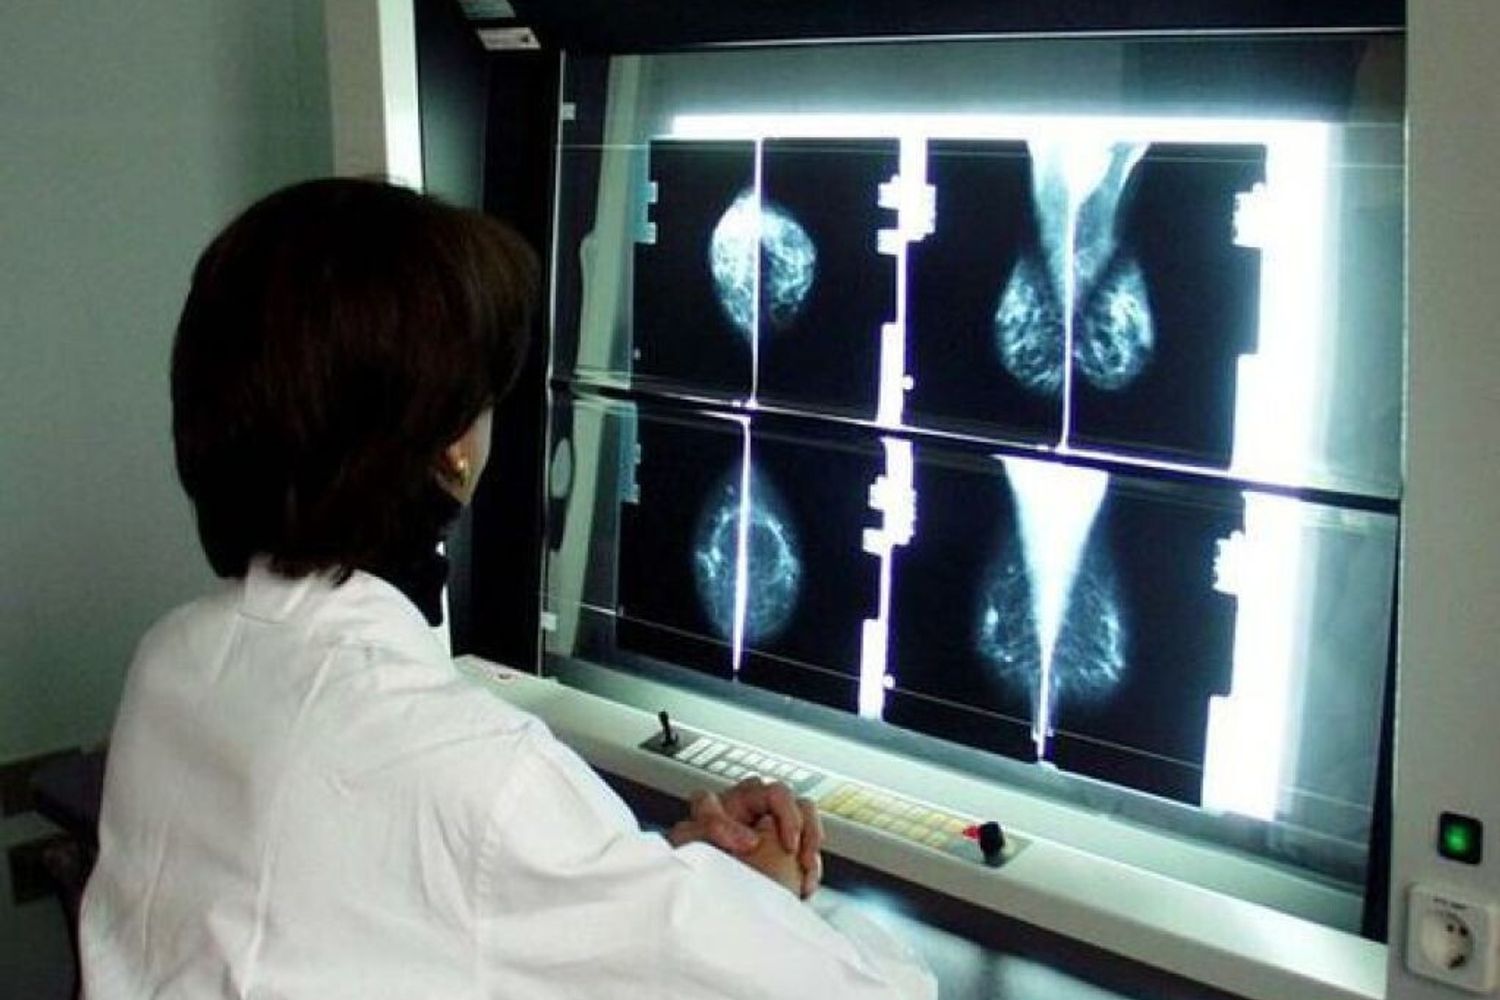

Chi deve fare esami a titolo di prevenzione o dopo avere superato un cancro, è meglio che non li faccia ora. Lo spiega all’AGI il professor Giuseppe Curigliano, direttore della divisione ‘Sviluppo di nuovi farmaci e terapie’ allo Istituto europeo oncologico di Milano: “Una persona che non ha un tumore attivo o perché fa dei semplici controlli o perché segue una terapia adiuvante precauzionale, come può essere quella ormonale, non viene considerato un’urgenza. Per cui, in un momento in cui il rischio epidemico è molto alto, è un paziente che deve entrare in ospedale il meno possibile perché se lo vedi ora o tra 3 o 4 mesi non cambia nulla”.

L’assistenza è garantita per “i malati di nuova diagnosi che devono fare un intervento, chi ha un tumore metastatico, chi ha un tumore troppo grande per essere operato e deve fare una terapia preparatoria, chi è stato malato e deve fare terapia post operatoria. Tutte queste persone non possono subire ritardi e non li subiranno”.